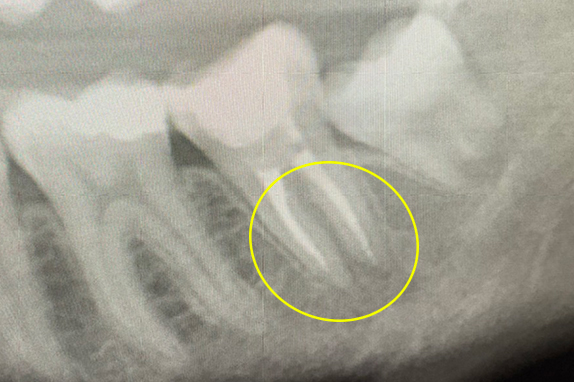

日本での根管治療の問題点

日本での根管治療の成功率について、東京医科歯科大学が調べたデータ(根管処置歯における根尖部X洗透過像の発現率 調査期間:2005年9月~2006年12月)というものがあります。根管治療を終えた後の歯が、どのくらいの割合で歯根の先に膿を持っているかという調査をしました。

その調査の結果、日本の根管治療の失敗率は50~70%であったという事実が分かりました。

裏を返せば、日本における一般的な根管治療の成功率は30~50%しかないと言えます。

歯ぐきがよく腫れる主訴で来院。レントゲン写真の術前を見ると大きな影が確認できます。この部分に嚢胞(のうほう)がある状態です。マイクロエンドと歯根周囲掻爬(歯周外科)をすることで改善したケースです。